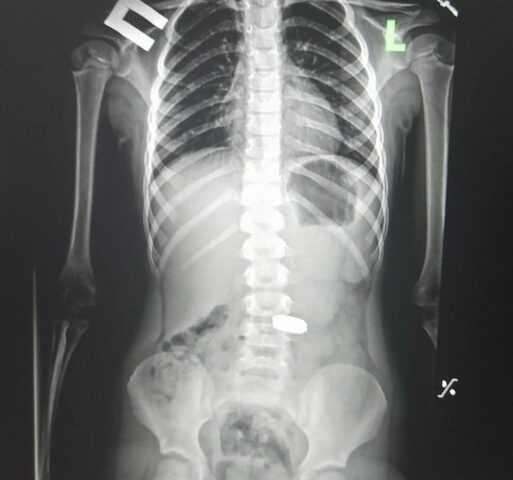

До медзакладу Мирославу ушпиталили зі скаргами на болі у шлунку. Рентген показав, що дівчина проковтнула п’ять монет. Серед них монети – номіналом одна гривня, 50 копійок.